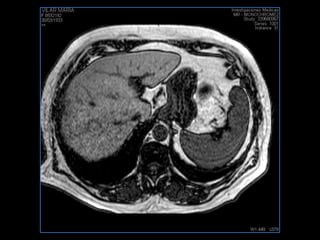

PROTOCOLO abdomen COR T2, AXIAL supresion grasa AX T1 +SAG T2  CON   GADOLINIO :  COR T1+AX T1(DIN) SAT: NO  FASE: RL THK: 6MM  COIL:  GAP: (FACTOR 1.4) 2MM FOV: 40 CM NEX:2 SINCRONIZACION RESPIRATORIA EN 3 O 4 CICLOS ALE

PROTOCOLO hígado graso AXIAL in phase y out phase AX T1 y AX fat sat +SAG T2  CON   GADOLINIO :  COR T1+AX T1(DIN) SAT: NO  FASE: RL THK: 4MM  COIL:  GAP: (FACTOR 1.4)  FOV: 40 CM NEX:2 SINCRONIZACION RESPIRATORIA EN 3 O 4 CICLOS ALE

resonancia de abdomen